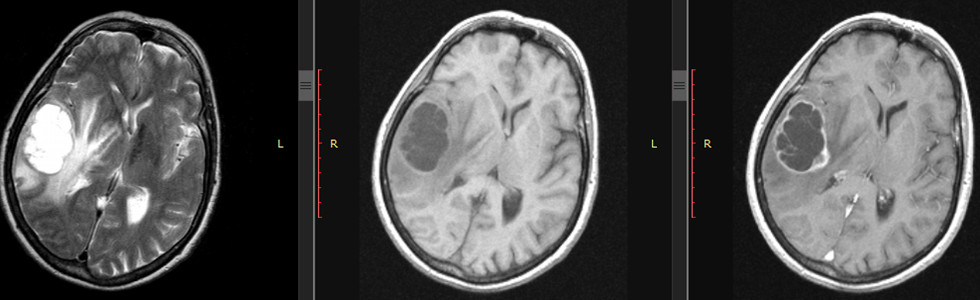

76-letnia kobieta od dwóch miesięcy zaczęła skarżyć się na bóle głowy. Rodzina zauważyła pewne spowolnienie psychoruchowe, nieadekwatne zachowanie. W ciągu ostatnich dwóch tygodni nudności, okresowo wymioty. Wykonane badanie rezonansu magnetycznego wykazuje zmiany jak na załączonych ilustracjach (od lewej): sekwencja T2 zależna, T1 zależna bez kontrastu, T1 zależna z gadoliną. Najbardziej prawdopodobne rozpoznanie to: